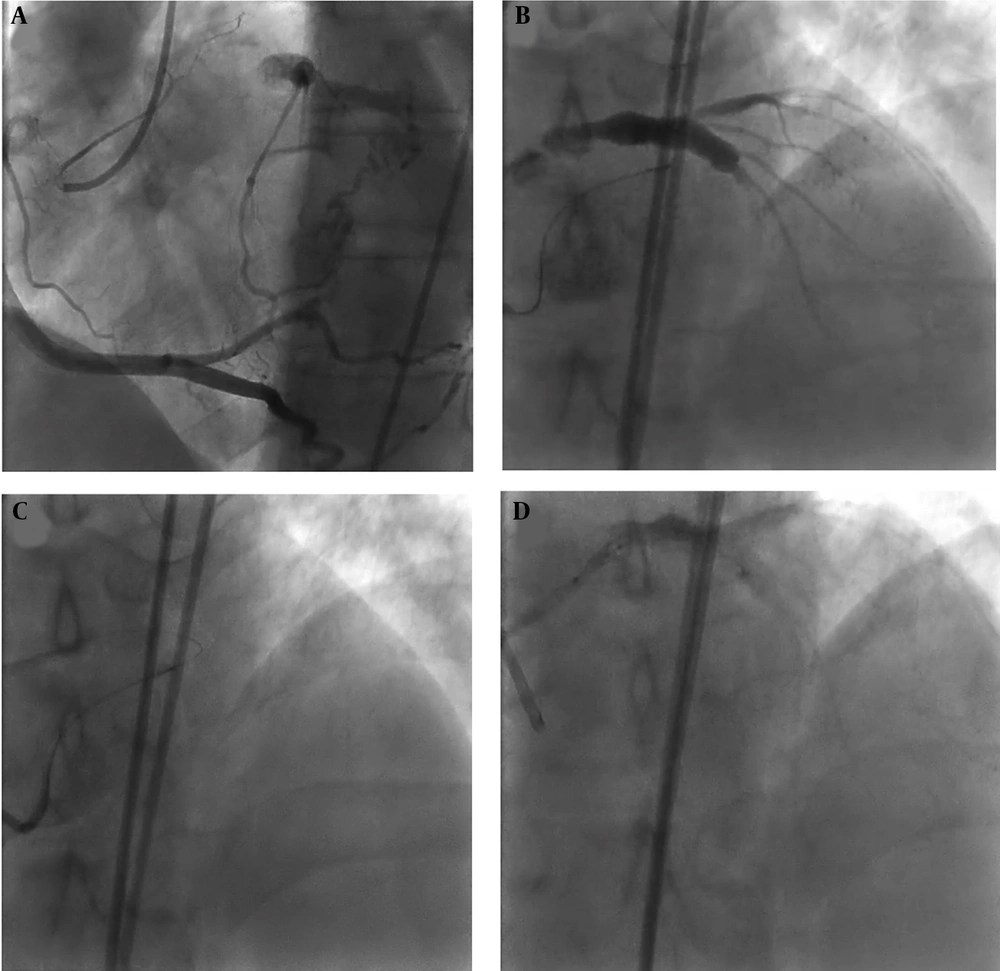

Lesion preparation and stenting: Sequential pre-dilatation was performed with a Ryurei Terumo 1.25 × 15 mm, Sapphire Orbus Neich 2.5 × 15 mm, and Accuforce Terumo 3.5 × 15 mm balloon. AXience Alpine Abbott 4.0 × 23 mm drug-eluting stent was deployed to cover the aorto-ostial LM segment, followed by final optimization and flaring using a Sapphire Orbus Neich 5.0 × 10 mm non-compliant balloon to achieve optimal apposition (Figure 3).

Dual access injection showed left main chronic total occlusion (LM CTO) which was filled via retrograde approach through right coronary artery (A, B), then left main-left anterior descending artery (LM-LAD) was wired via septal branches of right coronary artery with black SION (C), then percutaneous coronary intervention (PCI) on LM-LAD was done (D).